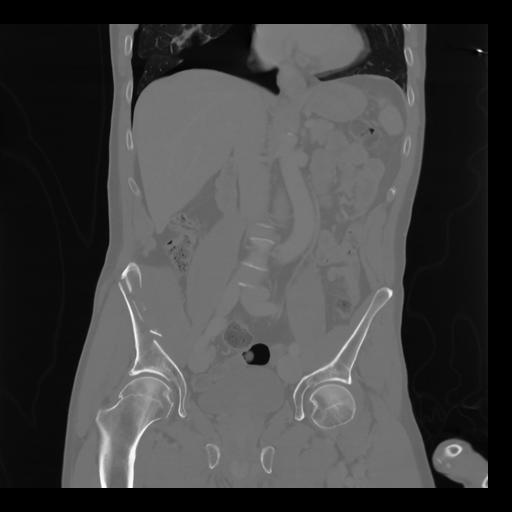

35 CUERPO,CE,Coronal,3.000,CUERPO,Coronal,